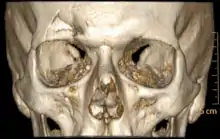

Лобна пазуха зазвичай парна, але рідко симетрична, на рентгенограмах її видно у формі нерівномірних пелюсток, розвернутих тонкою частиною донизу, які відкриваються у відповідні половини носа. Лобна пазуха може бути однією порожниною або мати численні комірки, поділяючи пазуху на окремі відсіки. Перегородка між двома лобними пазухами рідко буває рівна, часто одна пазуха більш розвинена інша пазуха менш розвинена, а у 1 % відсутня з однієї сторони[3]. Комірки та перегородки пазухи вистелені слизовою оболонкою та мають сполучення з порожниною носа. Передня стінка лобної кістки зазвичай дуже тоненька, що часто сприяє вдавленим переломам лобної кістки при травмах голови або умисних ударах у ділянку лоба.